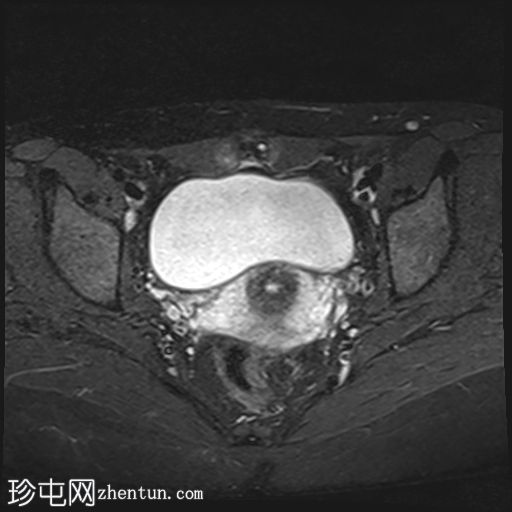

轴位

T2血流加权像

MRI特征符合剖宫产术后瘢痕子宫内膜异位症,表现为特征性T1高信号伴T1FS持续存在,T2低信号伴内部高信号灶,病灶边缘浸润于腹前壁肌肉内,以及对比增强。

该病灶累及腹白线并浸润腹直肌,主要位于中线左侧,耻骨联合及结节处腹直肌起点上方。

影像学表现符合病灶内出血成分,提示既往剖宫产瘢痕处存在异位子宫内膜组织。

在磁共振成像(MRI)上,瘢痕子宫内膜异位囊肿通常表现出与盆腔子宫内膜异位病灶相似的影像学特征。值得注意的是,它们在脂肪抑制T1加权像上表现为高信号强度区域,对应于异位子宫内膜腺体和出血。